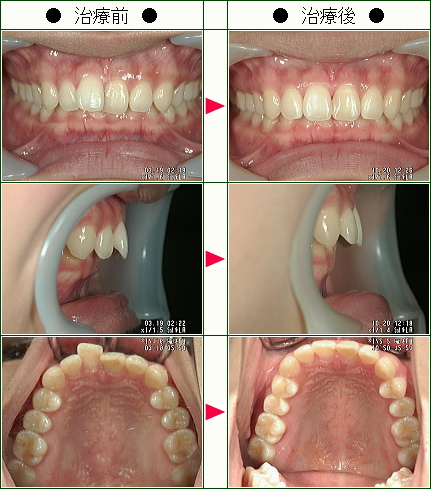

☆歯のデコボコ矯正症例(M.K.様 35歳 女性)